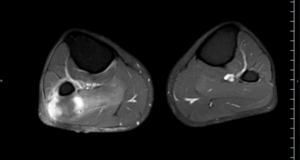

RM Pierna Derecha. Secuencia T1, corte axial.

RM Pierna Derecha. Secuencia T2, corte axial

RM Miembros Inferiores. Secuencia T1 supresión grasa con contraste IV, corte axial